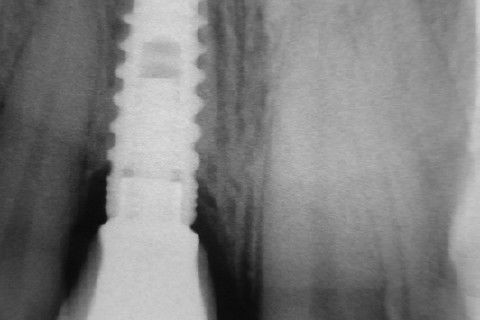

Controle radiográfico